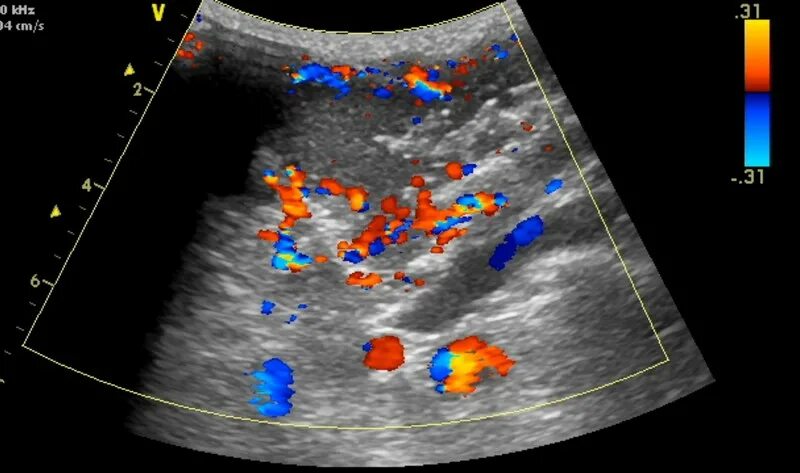

Локусы при цдк что это